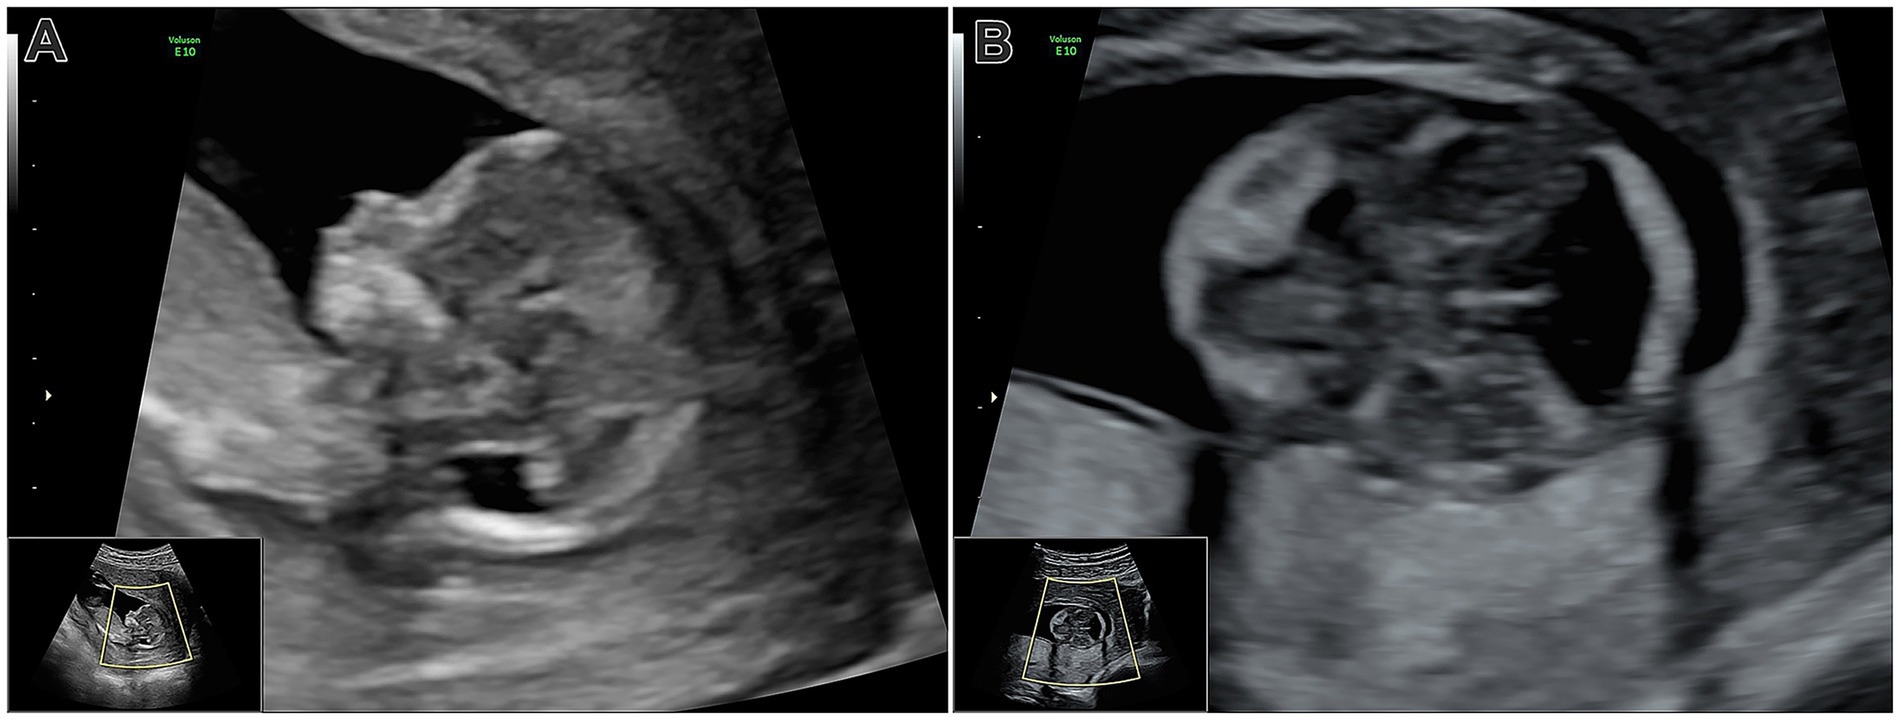

A 34-year-old woman (gravida 2/para 0) in her second pregnancy was admitted to the Obstetrics and Gynecology Clinic, University Hospital Ostrava, for a scheduled abortion in the 14th gestational week. The first pregnancy resulted in a missed abortion earlier in the same year without any known cause. During the second pregnancy, she had regular antenatal check-ups with no history of epilepsy, diabetes mellitus, hypertension, cardiac disease, bronchial asthma, or blood transfusion. There was no history of consanguinity, family history of malformations, or significant drug intake. The first-trimester screening tests (fb-hCG, PPAP-A, and NT) were also negative. During her abdominal ultrasound, performed as part of a routine check at 13 weeks of gestation, a posterior cranial fossa malformation was detected, resulting in a suspicion of a Dandy–Walker syndrome (Figure 1) and a recommendation for abortion along with a genetic examination. The patient agreed, and an abortion using misoprostol was induced, which finished without the need for a surgical revision.

Figure 1

Figure 1. (A) Ultrasonography at week 13, mid-sagittal view: Pathological appearance of the posterior cranial fossa, showing the diencephalon and brainstem. The enlarged posterior fossa and fourth ventricle are visible, but intracranial translucency is absent. (B) Transverse view of the skull base: The posterior fossa lacks the typical parallel lines of the brainstem and choroid plexus, with fourth ventricle dilation evident.